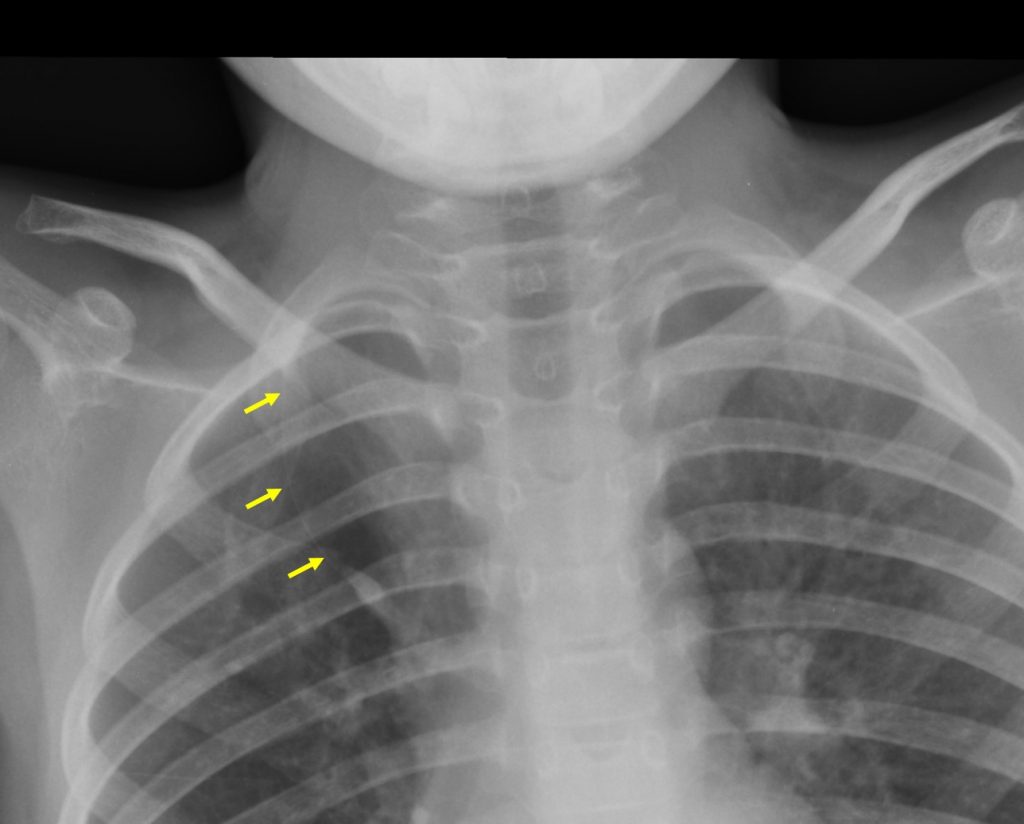

Pulmonary tuberculosis Radiology Cases